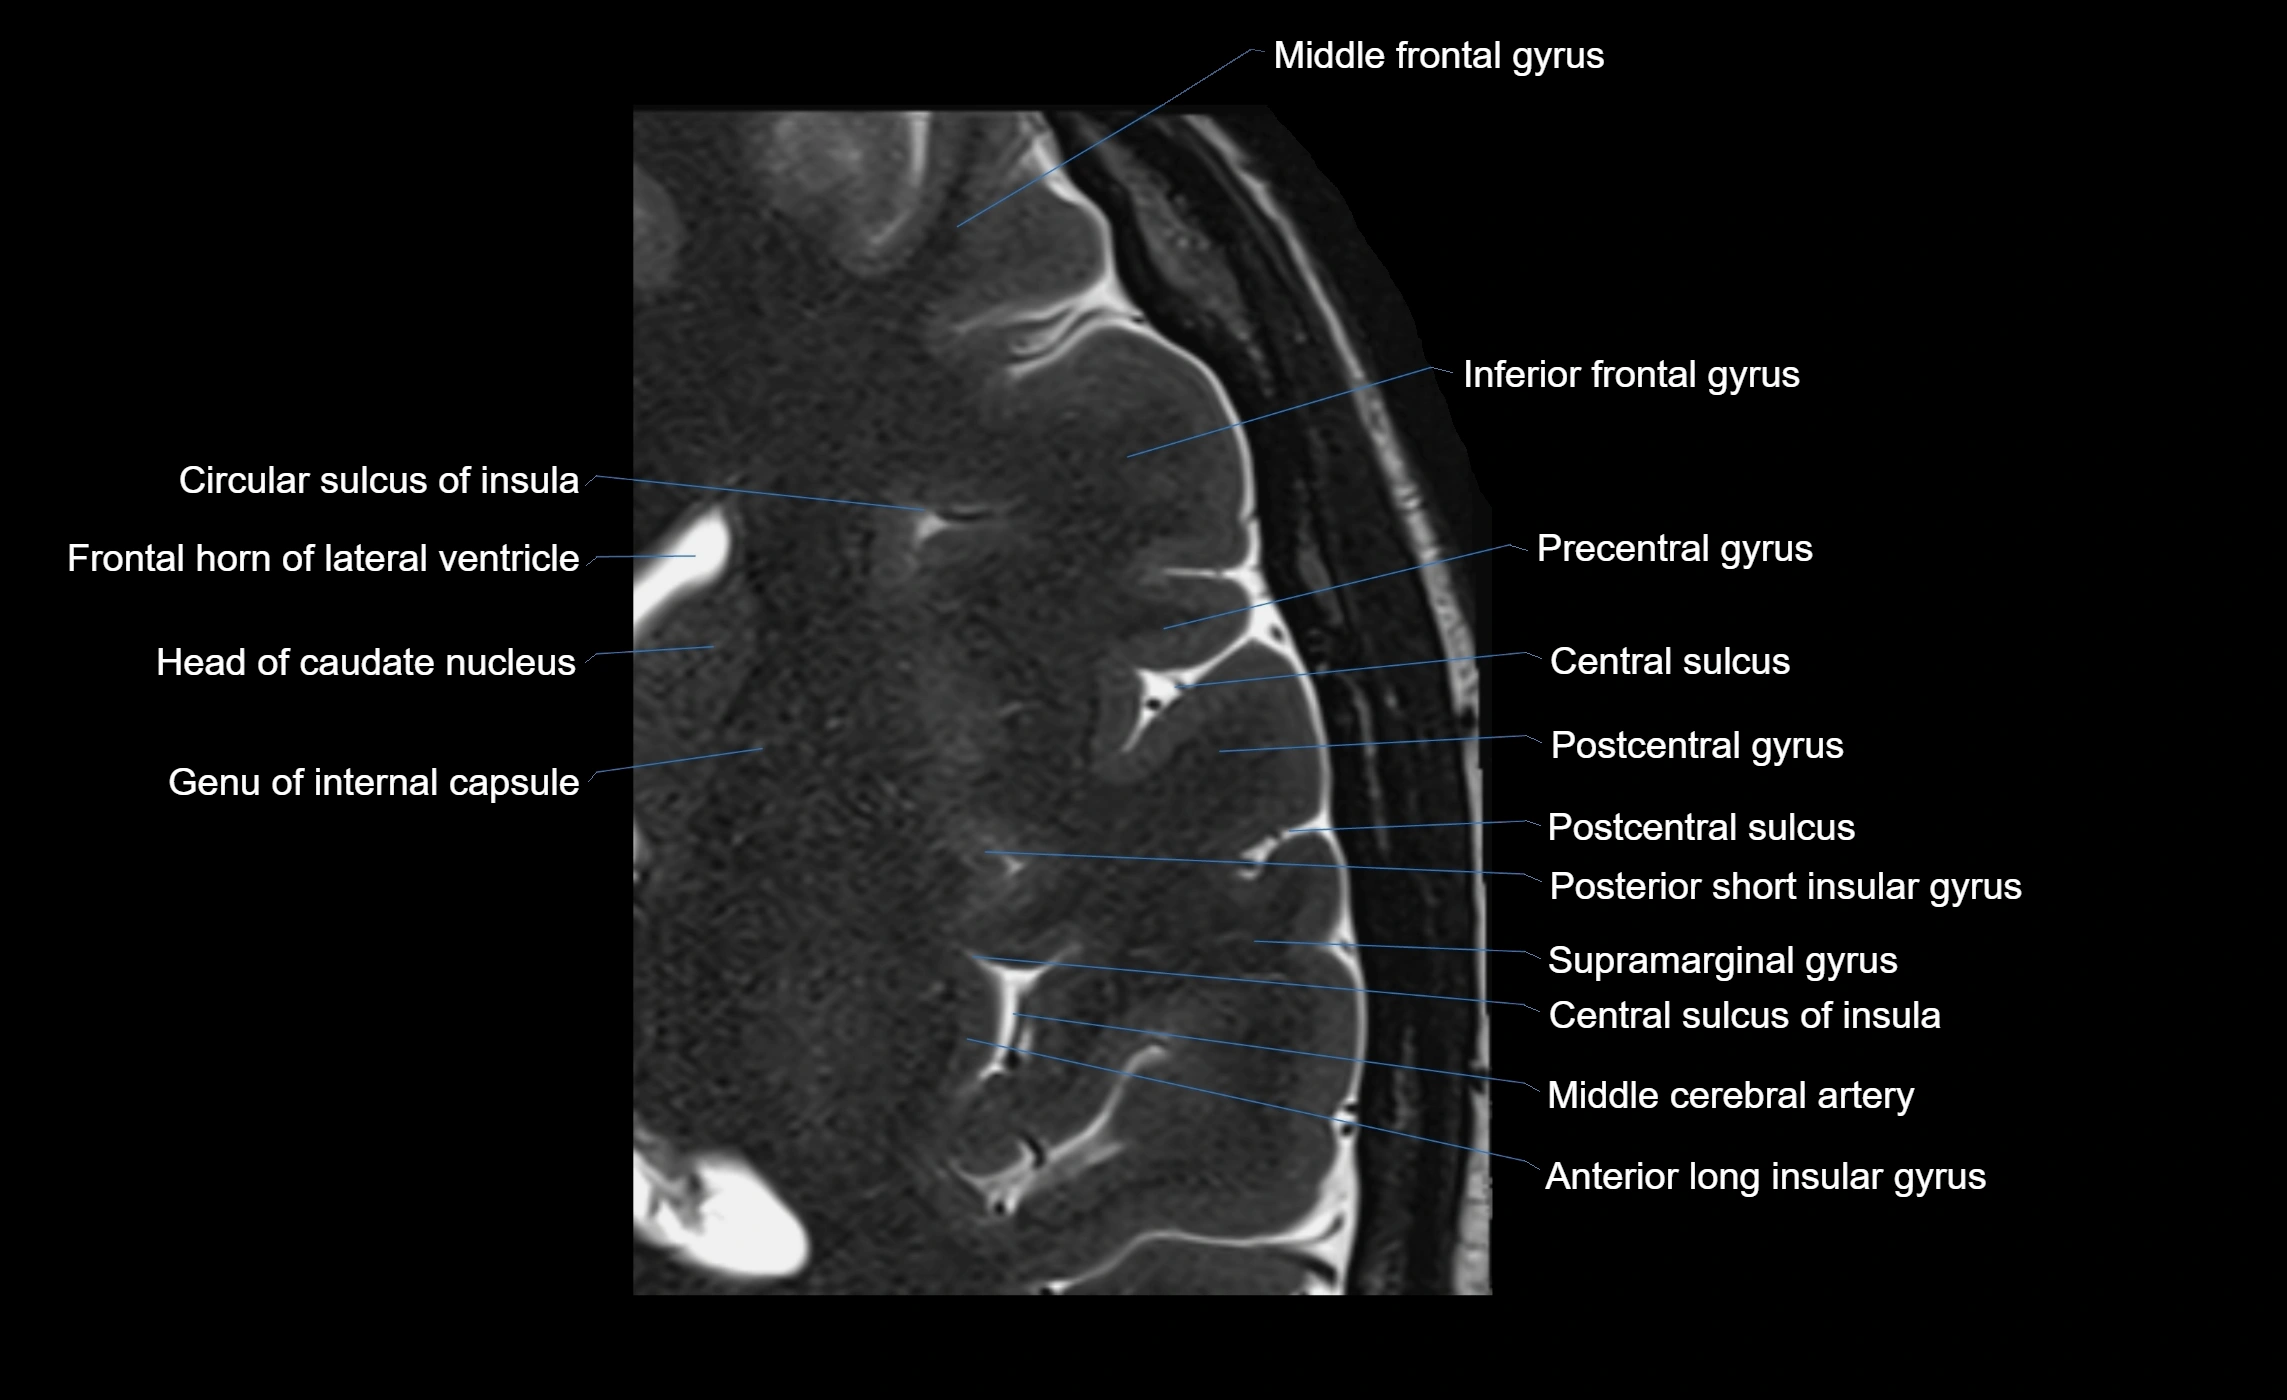

The anterior ascending ramus of the Sylvian fissure is a significant anatomical landmark in the lateral surface of the cerebral hemisphere. It represents one of the key branches of the Sylvian fissure (also known as the lateral sulcus) and plays an essential role in demarcating the boundaries between important cortical regions, notably within the frontal and parietal lobes. Understanding its anatomy and imaging appearance is crucial in neuroradiology, neurosurgery, and neuroanatomy for accurate localization and identification of adjacent brain structures.

• The anterior ascending ramus is a short, superiorly oriented branch that arises from the main stem of the Sylvian fissure.

• It projects upward (anteriorly and slightly dorsally) from the lateral sulcus into the inferior frontal gyrus.

• This ramus separates the pars opercularis (opercular part) from the pars triangularis (triangular part) of the inferior frontal gyrus.

• The anterior ascending ramus marks the boundary between Broca's area and adjacent cortical areas in the dominant hemisphere.

• Supplied predominantly by branches of the middle cerebral artery (MCA), particularly its opercular branches.

• The MCA runs within the Sylvian fissure and provides small cortical branches to adjacent gyri and sulci.

• Drained by superficial Sylvian veins (also called superficial middle cerebral veins), which follow the course of the Sylvian fissure.

• Venous blood ultimately drains into the sphenoparietal sinus and cavernous sinus.

MRI Appearance

• T1-weighted imaging:

• The Sylvian fissure and its anterior ascending ramus appear as low-signal intensity (dark) CSF-filled clefts between the gyri.

• Clear demarcation between adjacent gray and white matter.

• T2-weighted imaging:

• The fissure, including the anterior ascending ramus, is hyperintense (bright) due to CSF signal.

• Better visualization of the separation between opercular and triangular parts of the inferior frontal gyrus.